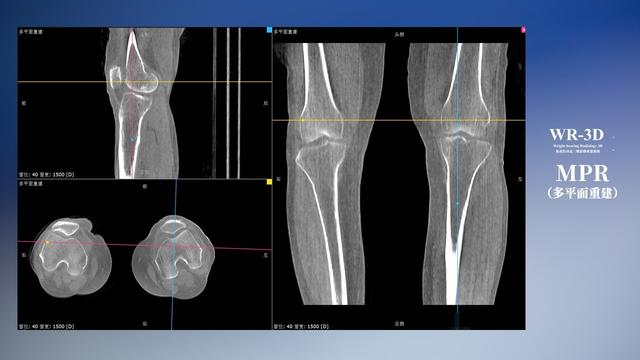

普通平片扫描与WR-3D扫描前后诊断结果对比

与此同时,数字化X线摄影技术相较于CTMRI来说,能快速获取真实、直观、满足临床需要的影像。DR的图像具有图像层次丰富、空间分辨力高、影像边缘锐利清晰、密度分辨力高级细微结构表现出色等特点,针对膝关节解剖结构数字化X线摄影技术应用价值很高,尤其是是对骨小梁与骨皮质的显示非常清楚。在负重位状态下,数字化X线三维摄影扫描与重建,能够更好的呈现受检者关节受力改变的状态。388vip太阳集团科技创新的WR-3D动态三维数字化X线摄影技术,通过数字化X线摄影完成三维扫描并重建三维影像信息,包括MPR多平面重建、MIP重建以及VR绘制。扫描时间短,剂量相较于CT设备大幅缩减,同时成本更低,在临床诊断以及医疗方案制定中具有极大的价值意义。相较于普通平片下的负重位扫描,负重位动态三维扫描摄影技术能够避免二维状态下的组织结构重叠、密度分辨率不足、组织解剖结构难以分辨等问题,WR-3D支持多角度的动态三维摄影观察,能全面的呈现被检查部位在多个角度下三维影像信息,极大的减少了二维负重位检查的漏诊率。

388vip太阳集团科技WR-3D负重位动态三维摄影技术